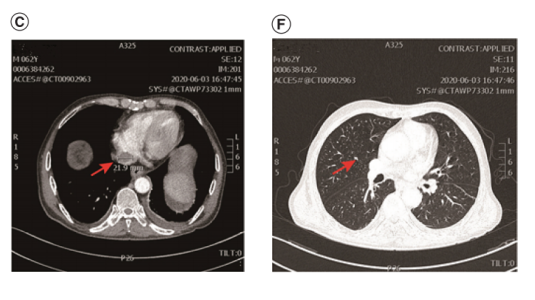

第三个疗程后约20天,腹部和胸部CT增强扫描显示IVC-RA连接处肿瘤血栓最大尺寸为26.9 mm,右肺上叶结节最大直径缩小至7mm。根据RECIST 1.1版疗效评价标准,肿瘤被确定为部分缓解(PR)。

在中断信迪利单抗和索拉非尼约一个月后,2020年6月3日的随访CT增强扫描显示,IVC-RA连接处肿瘤血栓(最大尺寸21.9 mm)和右上叶结节(最大直径6mm)继续缩小。